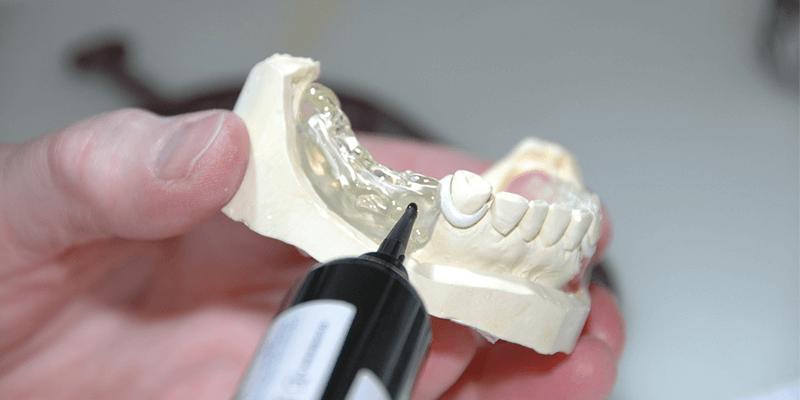

Doch auch in jüngeren Jahren kann es zu Verlusten von Zähnen kommen. Was noch viel häufiger der Fall ist, ist die Notwendigkeit von Zahnfüllungen. Die wenigsten Menschen hierzulande können ein gesundes Gebiss ohne jede Zahnfüllung aufweisen. Zahnfüllungen gehören zu den am meisten angewendeten zahnärztlichen Maßnahmen des Zahnerhalts, besonders, wenn es um Karies geht. Ist die Schädigung von Zähnen zu weit vorangeschritten, dann ist für den Zahnerhalt oft eine Verkronung von Zähne n eine gute Lösung. Der Zahn wird dann beschliffen, bleibt mit der Zahnwurzel erhalten und wird mit einer Krone überzogen, die ihn natürlich aussehen lässt und vor dem Zahnverlust schützt.

Für Zahnersatz, Füllungen und Kronen stehen der modernen Zahnmedizin sehr viele verschiedene Materialien zur Verfügung. Dazu gehören Keramik, Gold, Goldlegierungen, Amalgam, Titan und Kunststoff. Das Ziel der ständigen Verbesserung der technischen Möglichkeiten für Zahnersatz und Zahnfüllungen ist natürlich vor allem, eine lange Haltbarkeit zu erreichen. Gleichzeitig sollen Zahnersatz und Zahnfüllungen gut verträglich sein, und so gut wie möglich will man sie dem Aussehen der natürlichen Zähne angleichen. Besonders gut gelingt letzteres mit der Keramik, weil sie lichtdurchlässig ist, keine Verfärbungen zeigt und gut den Belastungen standhält. Doch auch der Kunststoff hat in der Zahnmedizin aufgeholt. Moderne Kunststoffe für Zahnfüllungen und Zahnersatz sind entschieden fester und länger haltbar, als das früher der Fall war.

Selbst sehr hochwertige und moderne Kunststoffe sind in der Regel preisgünstiger als beispielsweise Keramik oder Goldlegierungen. Zwar zeigen Kunststoffe noch immer einen etwas stärkeren Abrieb als manche andere Füllungen und Ersatzmaterialien für Zähne, doch ist inzwischen eine ausgezeichnete Haltbarkeit erreicht. Um eine bessere Härte zu erreichen, werden heuten den Kunststoffen für Zahnersatz und Kronen Quarz, Glas und andere Zusätze hinzugefügt, die den Kunststoff zusätzlich härten. Hinzu kommt, dass sich inzwischen die Kunststoffe auch farblich den natürlichen Zähnen sehr gut anpassen lassen. Kunststoff ist nicht lichtdurchlässig wie Keramik. Daher kann es auch bei sehr guter Anpassung noch immer leichte Unterschiede geben, doch sind die teils schon verschwindend gering. Besonders unauffällig wirkt ein Zahnersatz aus diesem Material, wenn eine Prothese daraus gefertigt wird, eine Teilprothese oder die Verblendung mit mehreren Kronen im vorderen Gebiss.